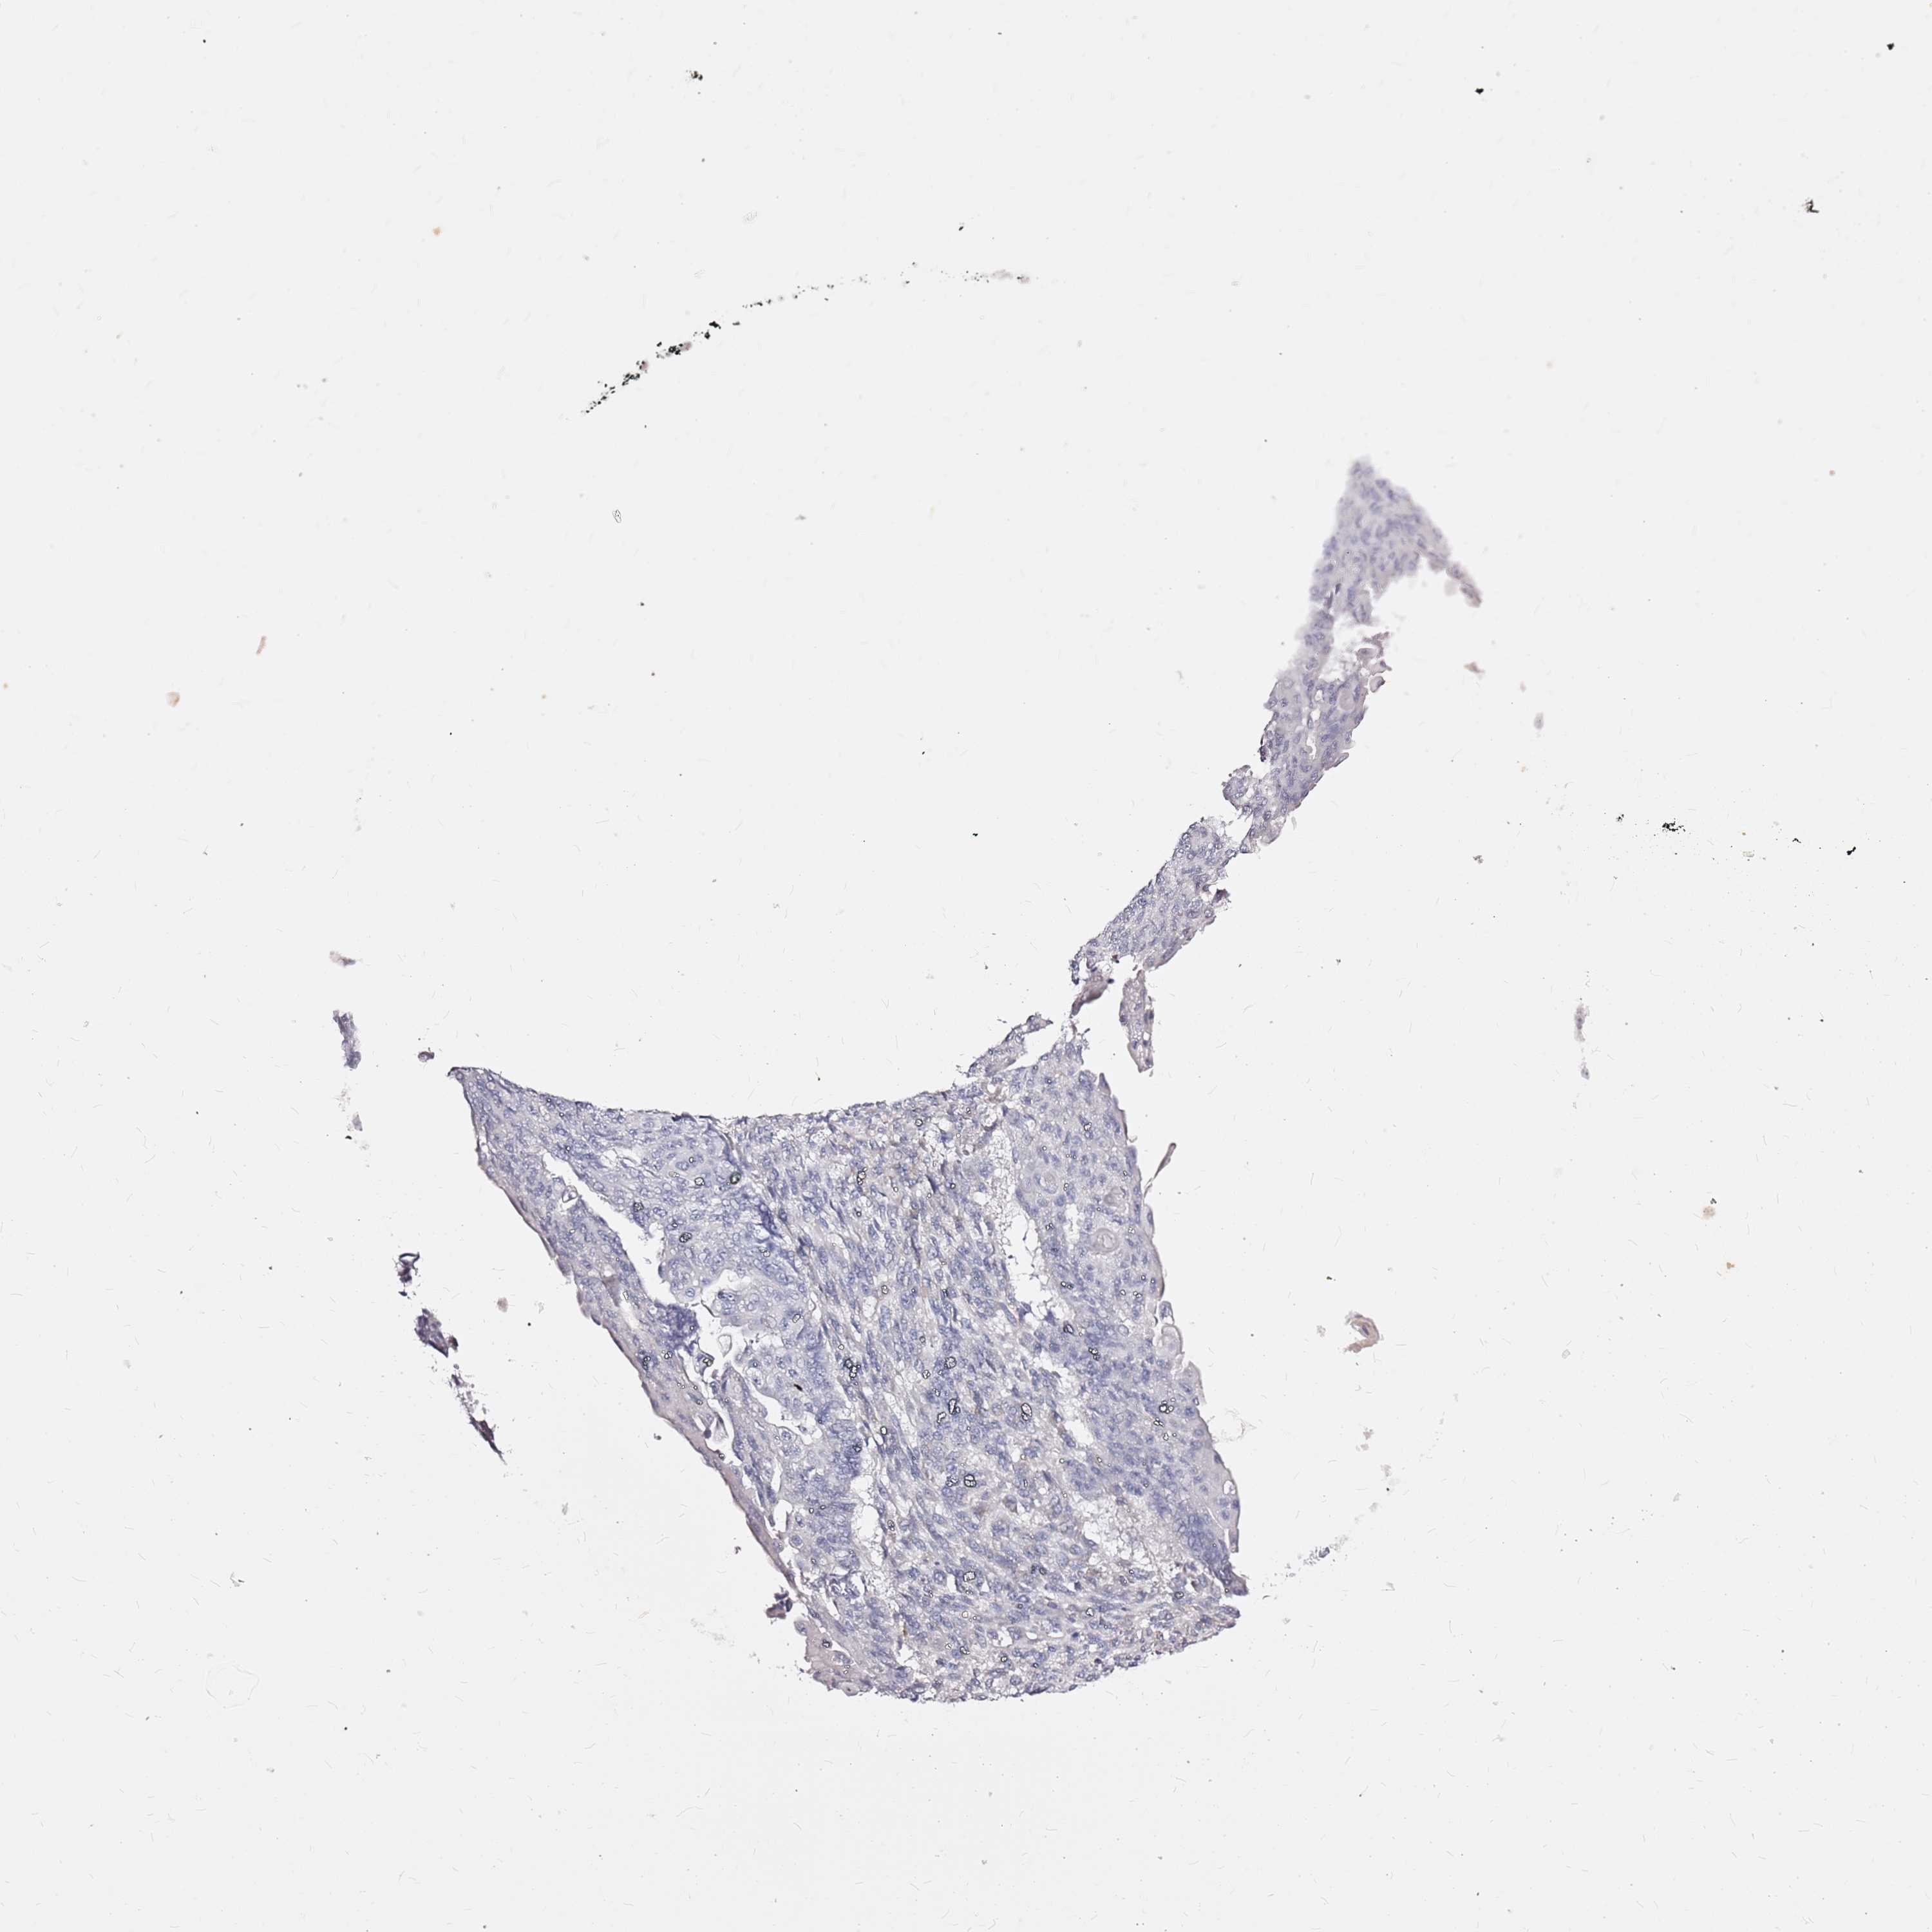

ENDOMETRIAL CANCER - Protein expressioni

A mouse-over function shows sample information and annotation data. Click on an image to view it in a full screen mode. Samples can be filtered based on level of antibody staining by selecting one or several of the following categories: high, medium, low and not detected. The assay and annotation is described here.

Note that samples used for immunohistochemistry by the Human Protein Atlas do not correspond to samples in the TCGA dataset.

Antibody stainingi

Antibody staining in the annotated cell types in the current human tissue is reported as not detected, low, medium, or high, based on conventional immunohistochemistry profiling in selected tissues. This score is based on the combination of the staining intensity and fraction of stained cells.

Each image is clickable and will lead to virtual microscopy that enables deeper exploration of all samples and also displays staining intensity scores, fraction scores and subcellular localization as well as patient and tissue information for each sample.

Antibody HPA044404

Antibody HPA052908

Staining

High

Medium

Low

Not detected

Intensity

Strong

Moderate

Weak

Negative

Quantity

>75%

75%-25%

<25%

None

Location

Nuclear

Cytoplasmic/membranous

Cytoplasmic/membranous,nuclear

Adenocarcinoma, NOS